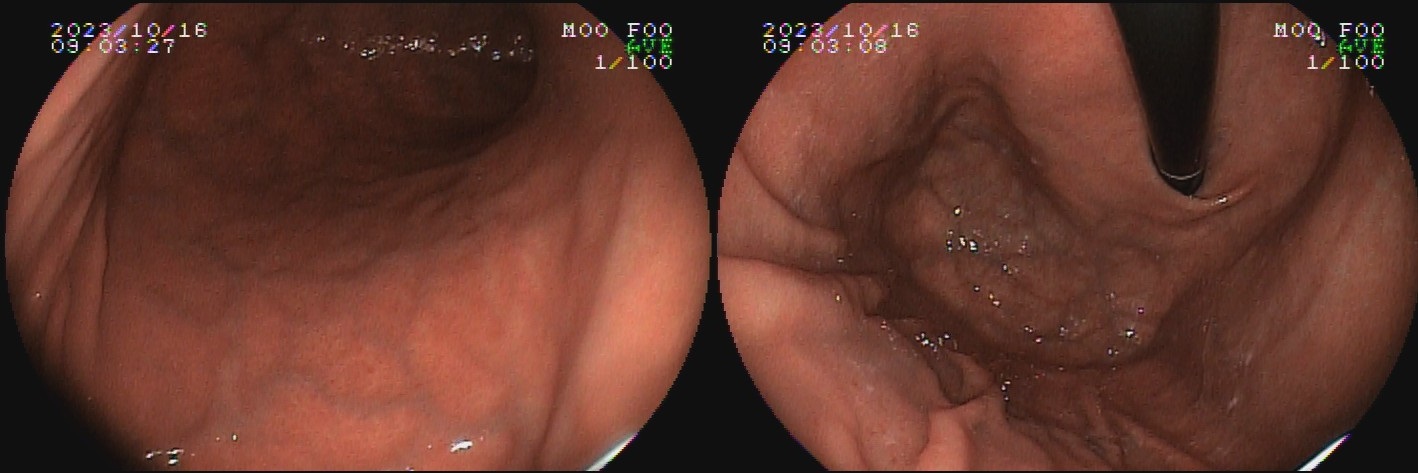

O termo gastrite crônica atrófica refere-se à atrofia da mucosa gástrica causada pelo H. pylori. Inicialmente, a mucosa sofre agressão por neutrófilos, e mais tardiamente, por monócitos. Com o tempo, essa agressão reduz a população de glândulas, tornando o relevo reduzido e a mucosa mais pálida. A diminuição da espessura da camada mucosa torna os vasos da submucosa mais evidentes ao exame endoscópico. Segundo a evolução descrita por Kimura-Takemoto, essa patologia tem início no antro e incisura angular (C1),  e progride em direção à cárdia pela pequena curvatura do corpo, e, após atingir a região mais proximal do estômago (C2 e C3), a progressão inicia abertura da região acometida, expandindo-se em direção às paredes anterior e posterior do corpo e fundo simetricamente (O1 e O2), até acometer a grande curvatura (O3).